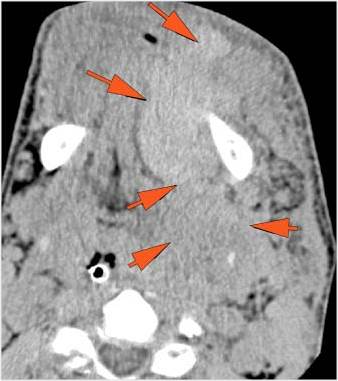

There is localized edema, hematoma or abscess within in the facial or scalp soft tissues, SMAS, infratemporal fossa, masticator space or oral cavity.

There is evidence of gas or a foreign body at a possible fracture site, indicative of an open or penetrating injury.

There is soft tissue swelling suggesting injury to the parotid or submandibular glands.

The upper airway is significantly narrowed or obstructed.